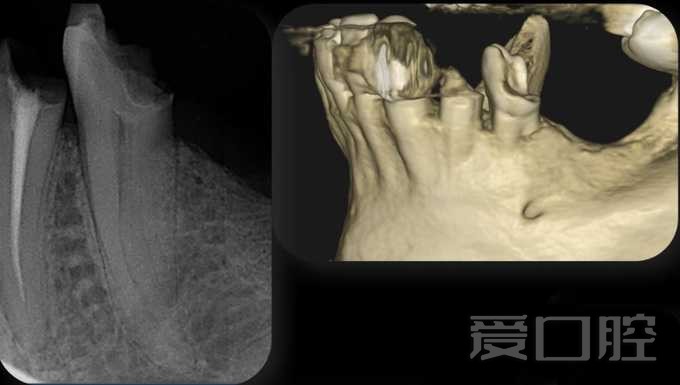

下颌第二前磨牙3根管1例